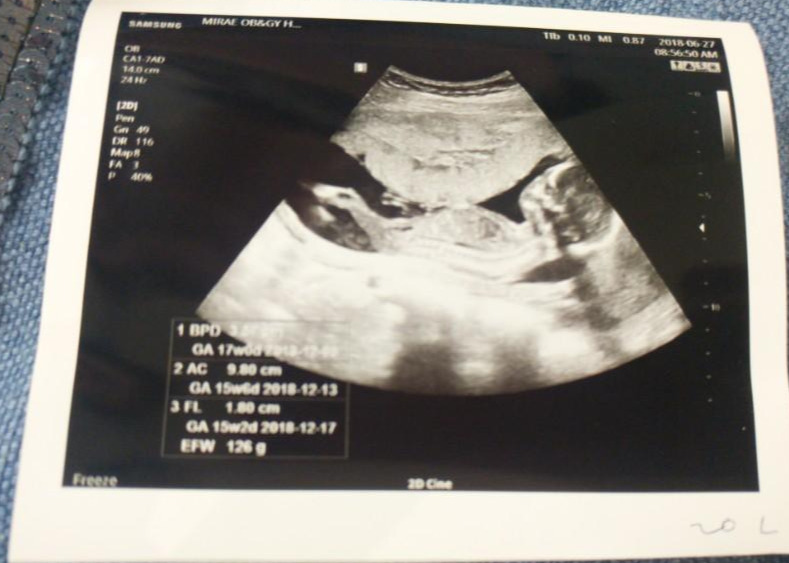

룰루&랄라. 랄라는 늘 초음파 카메라로 엄마를 또렷하게 쳐다본다. 룰루는 엄마가 TV볼 때처럼 항상 같은 자세로 눕방이다.